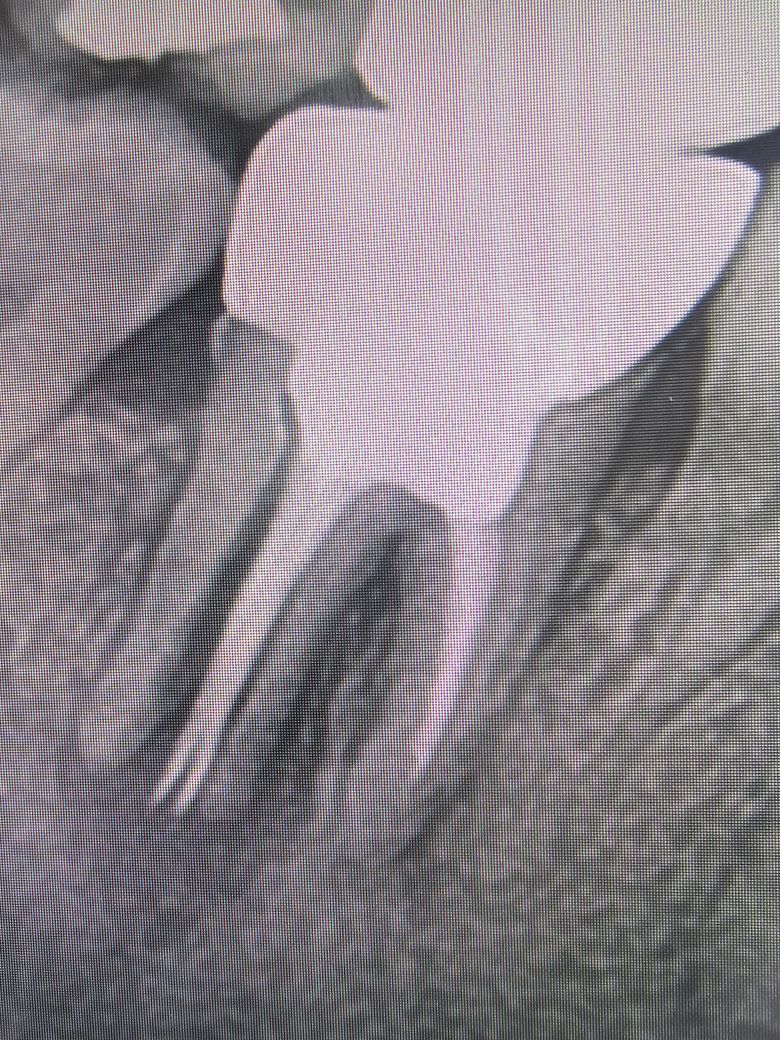

이 치아 꼭 임플란트 해야 하는건가요??

오른쪽 어금니인데 치아 뿌리가 x-ray상 저렇게 나오는데치과에서는 임플란트 해야 한다고 하네요. 통증은 아예 없는데, 그냥 쓰면 안되고 꼭 임플란트 해야 하는건가요?

사진상에 보이는 치아는 치아가 수직으로 깨진거 같습니다 .발치를 하시고 나서 임플란트를 하시는게 좋을것같습니다.

사진으로는 치아의 뿌리가 부러진것으로 보입니다. 치아의 뿌리가 부러진 경우에는 치아를 발치 해야 합니다

생니 아니고 치아뿌리 주위에 염증이 많이 진행되어 있어 지금도 뼈가 녹아있는 상태입니다. 두면 점점 더 뼈가 녹아 없어지기 때문에 가능한 빨리 치아를 뽑아 주어야 합니다. 임플란트는 그 다음 문제입니다.

엑스레이상 치아뿌리 하방 잇몸뼈로 염증은 있는 상태입니다 그냥 둘 경우 잇몸뼈가 점차 녹을 수 있습니다 발치를 원치 않는다면 치근단절제술 등을 고려해볼 수 있습니다